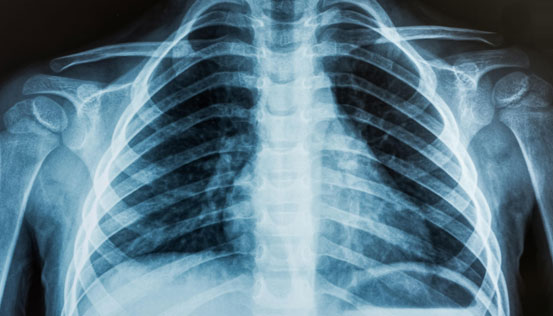

Radiographs or X-rays are a valuable diagnostic tool in medicine, providing insights into the body's internal structures and aiding in diagnosis of various medical conditions. It is essential in healthcare for detecting and monitoring injuries and diseases.

However, it is important to use X-rays judiciously due to their ionizing radiation. We at Insight Diagnostics take various measures to minimize radiation exposure to patients during X-ray procedures.